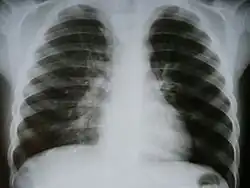

Инфильтра́т (от лат. in — в; filtratus — процеженный) — скопление в тканях организма клеточных элементов с примесью крови и лимфы. Наиболее часто встречаются воспалительный и опухолевый инфильтрат. Воспалительный инфильтрат состоит преимущественно из полиморфноядерных лейкоцитов (гнойный инфильтрат), эритроцитов (геморрагический инфильтрат), лимфоидных клеток (круглоклеточный инфильтрат), гистиоцитов и плазматических клеток (гистиоцитарно-плазмоклеточный инфильтрат) и других. Такие инфильтраты могут рассасываться, расплавляться, подвергаться склерозированию, с образованием каверны, абсцесса, рубца и тому подобного. Опухолевый инфильтрат состоит из опухолевых клеток различной природы (карцинома, саркома) и является проявлением инфильтрирующего роста опухоли. С образованием инфильтрата ткань увеличивается в объёме, меняет цвет, становится плотнее, иногда болезненна. В хирургической практике инфильтратом называется уплотнение, возникающее в тканях при их пропитывании анестезирующим (обезболивающим) раствором (смотри Местная новокаиновая блокада).